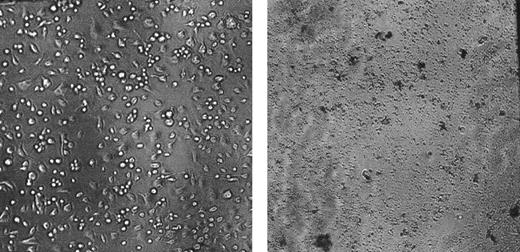

To investigate whether bystander cell destruction damaged not only hematopoietic cells but also stromal cells, we cotransplanted BM cells from BM failure CByB6F1 mice with BM cells from a healthy B6 codonor into lethally irradiated CByB6F1 recipients. Two weeks later, BM cells from humanely killed recipients were cultured in 96-well plates to develop feeder layers; at 4 weeks, they were overlaid with fresh BM cells from an untreated healthy CByB6F1 donor. For comparison, feeder layers were also established from BM cells of untreated healthy CByB6F1 mice, which were then overlaid with fresh BM cells from the same untreated healthy CByB6F1 donor. Stromal feeder layers that developed from normal CByB6F1 BM cells supported marrow cell growth (Figure 6, upper panel), but BM cells from cotransplantation recipients did not form a stromal feeder layer and thus could not support the growth of overlaid normal BM cells (Figure 6, low panel). These data indicate that BM cells from BM failure donors indiscriminately destroyed stromal cells from BM of healthy codonors, causing functional failure in the establishment of a feeder layer to support marrow cell growth (Figure 6, low panel).

Stromal cells as bystanders. BM cells from CByB6F1 mice treated with 5 Gy TBI and 5 × 106 B6 LN cell infusion 14 days earlier were mixed 1:2 with BM cells from a healthy B6 mouse, and the cell mixtures were then transplanted into new lethally irradiated CByB6F1 recipients. After 2 weeks, BM cells extracted from the recipients were cultured in α-MEM at 33°C with 5% CO2 along with BM cells from 2 fresh CByB6F1 mice to establish stromal feeder layers After 4 weeks in cell culture, fresh BM cells were overlaid on the established feeder layers. Stromal feeder developed from normal CByB6F1 marrow (left) supported marrow cell growth, but stromal cells from cotransplantation recipients could not establish a feeder layer to support marrow growth (right).